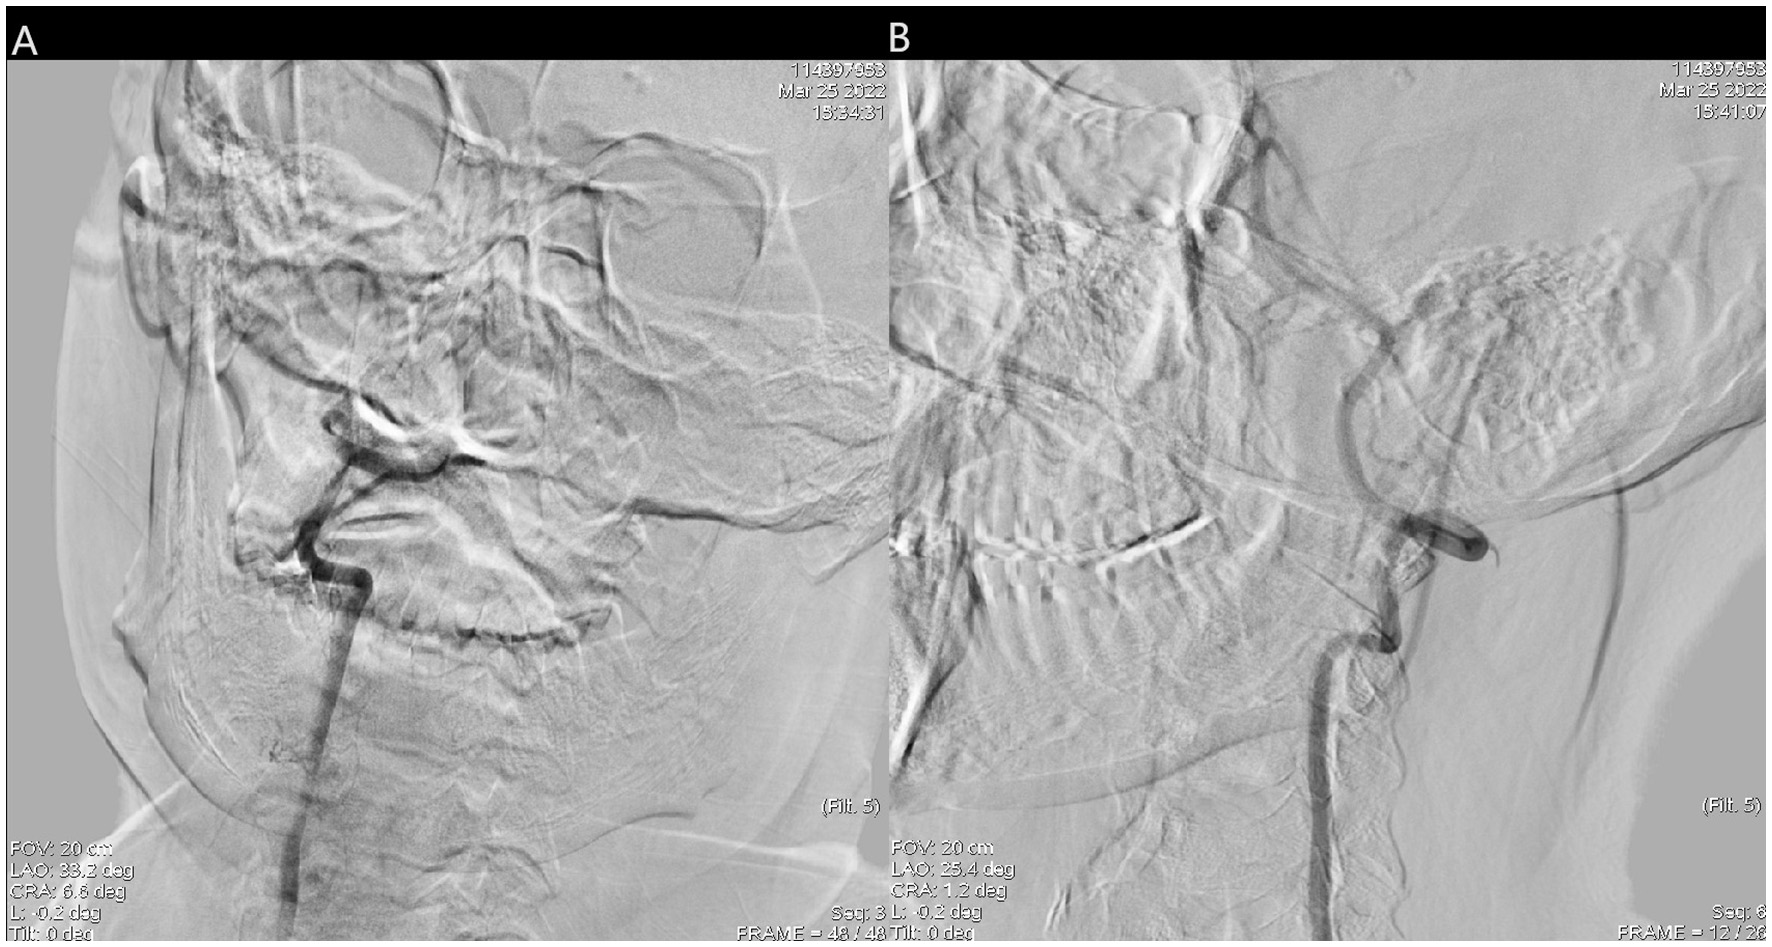

Figure 3

(A) Right vertebral artery was filling defect and (B) the blood flow of left vertebral artery and basilar artery was normal.